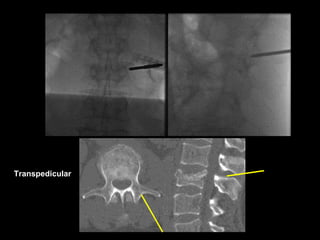

Inflatable ballon in the midline of the fractured body

Tip of the guide pin over the center of the vertebral body

Transpedicular